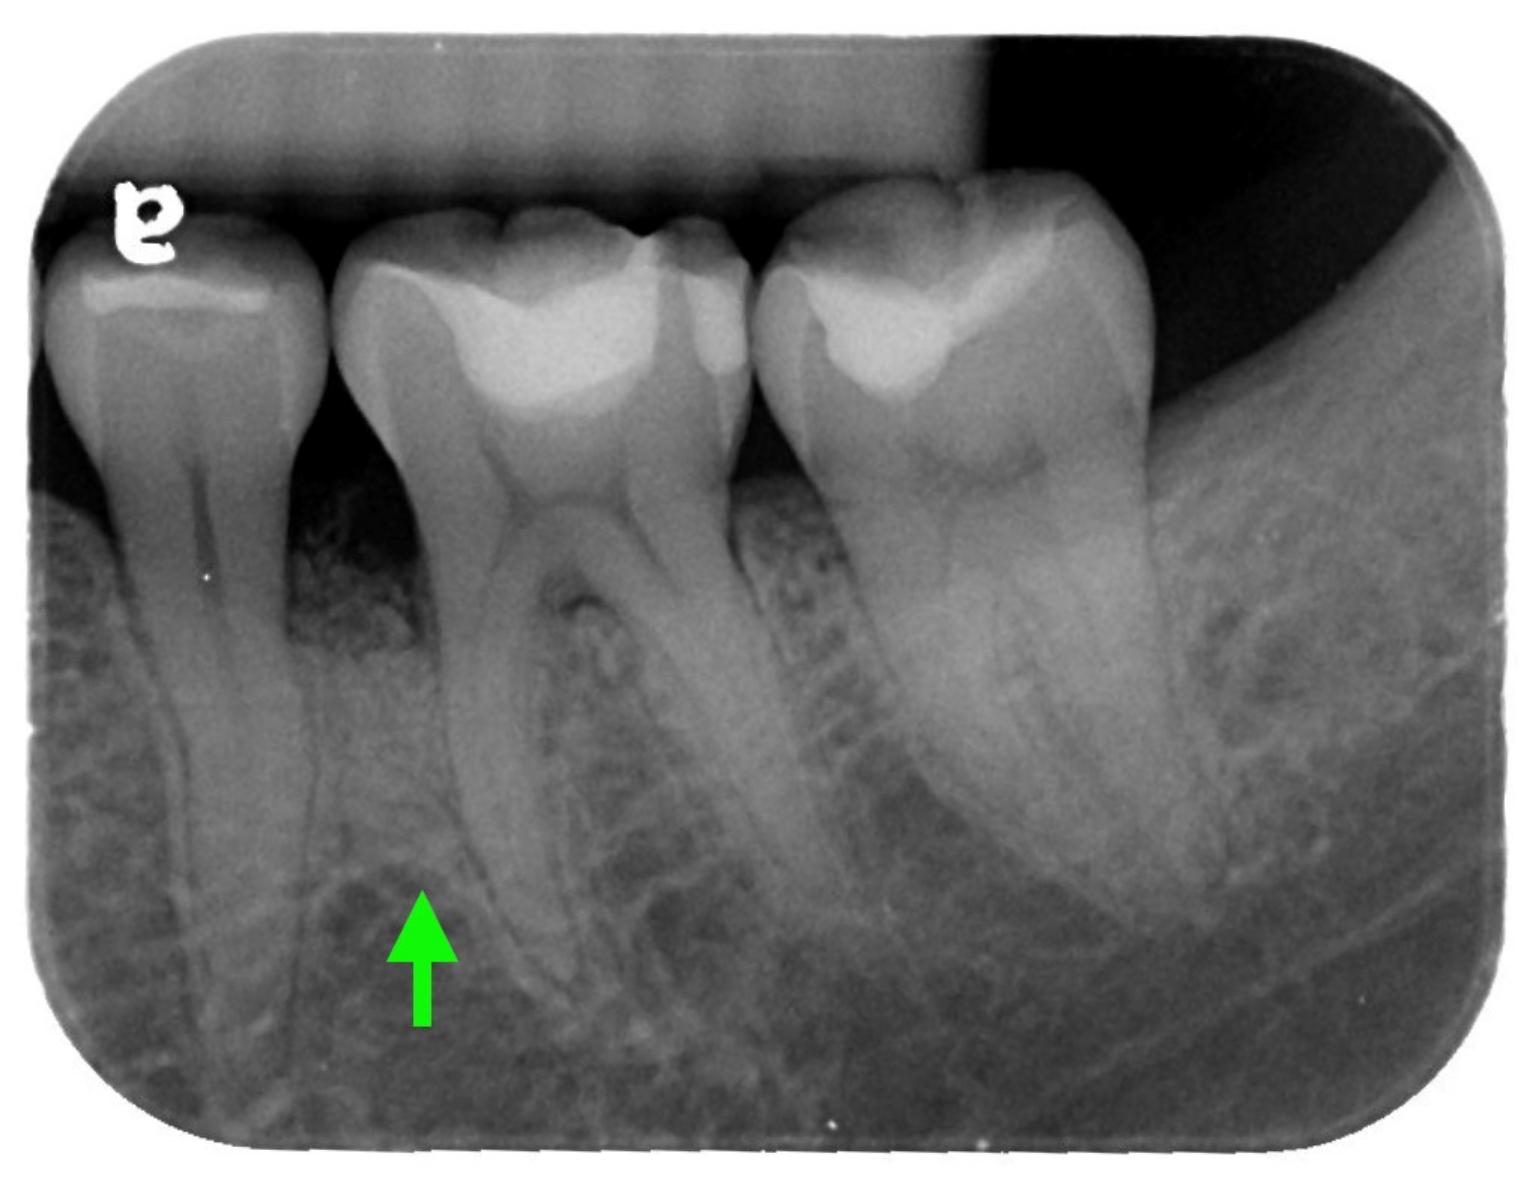

治療後一年追蹤:綠色箭頭處可見骨充填產生(圖片來源/新光醫院)